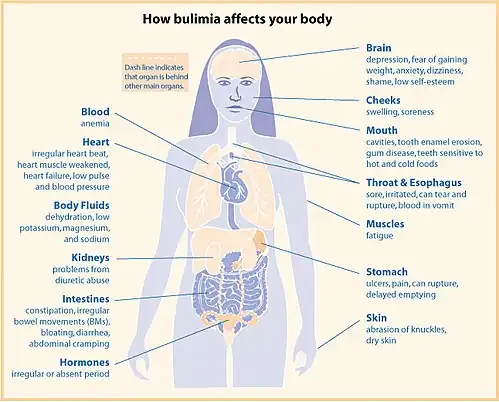

Signs and symptoms

Bulimia typically involves rapid and out-of-control eating, which is followed by self-induced vomiting or other forms of purging.[11][9] This cycle may be repeated several times a week or, in more serious cases, several times a day[12] and may directly cause:

- Dehydration

- Electrolyte imbalance can lead to abnormal heart rhythms, cardiac arrest, and even death

- Oral trauma, lacerations to the lining of the mouth or throat due to forced throwing up movements.[13]

- Russell's sign: calluses on knuckles and back of hands due to repeated trauma from incisors[14][15]

- Swollen salivary glands (in the neck, under the jawline)[16][17]

- Gastrointestinal problems, like constipation and acid reflux[13]

- Constipation or diarrhea

- Hypotension

- Infertility and/or irregular menstrual cycles

- Weight Fluctuations

People with bulimia are at a higher risk to have an affective disorder, such as depression or general anxiety disorder. One study found 70% had depression at some time in their lives (as opposed to 26% for adult females in the general population), rising to 88% for all affective disorders combined.[24] Another study in the Journal of Affective Disorders found that of the population of patients that were diagnosed with an eating disorder according to the DSM-V guidelines about 27% also suffered from bipolar disorder. Within this article, the majority of the patients were diagnosed with bulimia nervosa, the second most common condition reported was binge-eating disorder.[25] Some individuals with anorexia nervosa exhibit episodes of bulimic tendencies through purging (either through self-induced vomiting or laxatives) as a way to quickly remove food in their system.[26] There may be an increased risk for diabetes mellitus type 2.[27] Bulimia also has negative effects on a person's teeth due to the acid passed through the mouth from frequent vomiting causing acid erosion, mainly on the posterior dental surface.